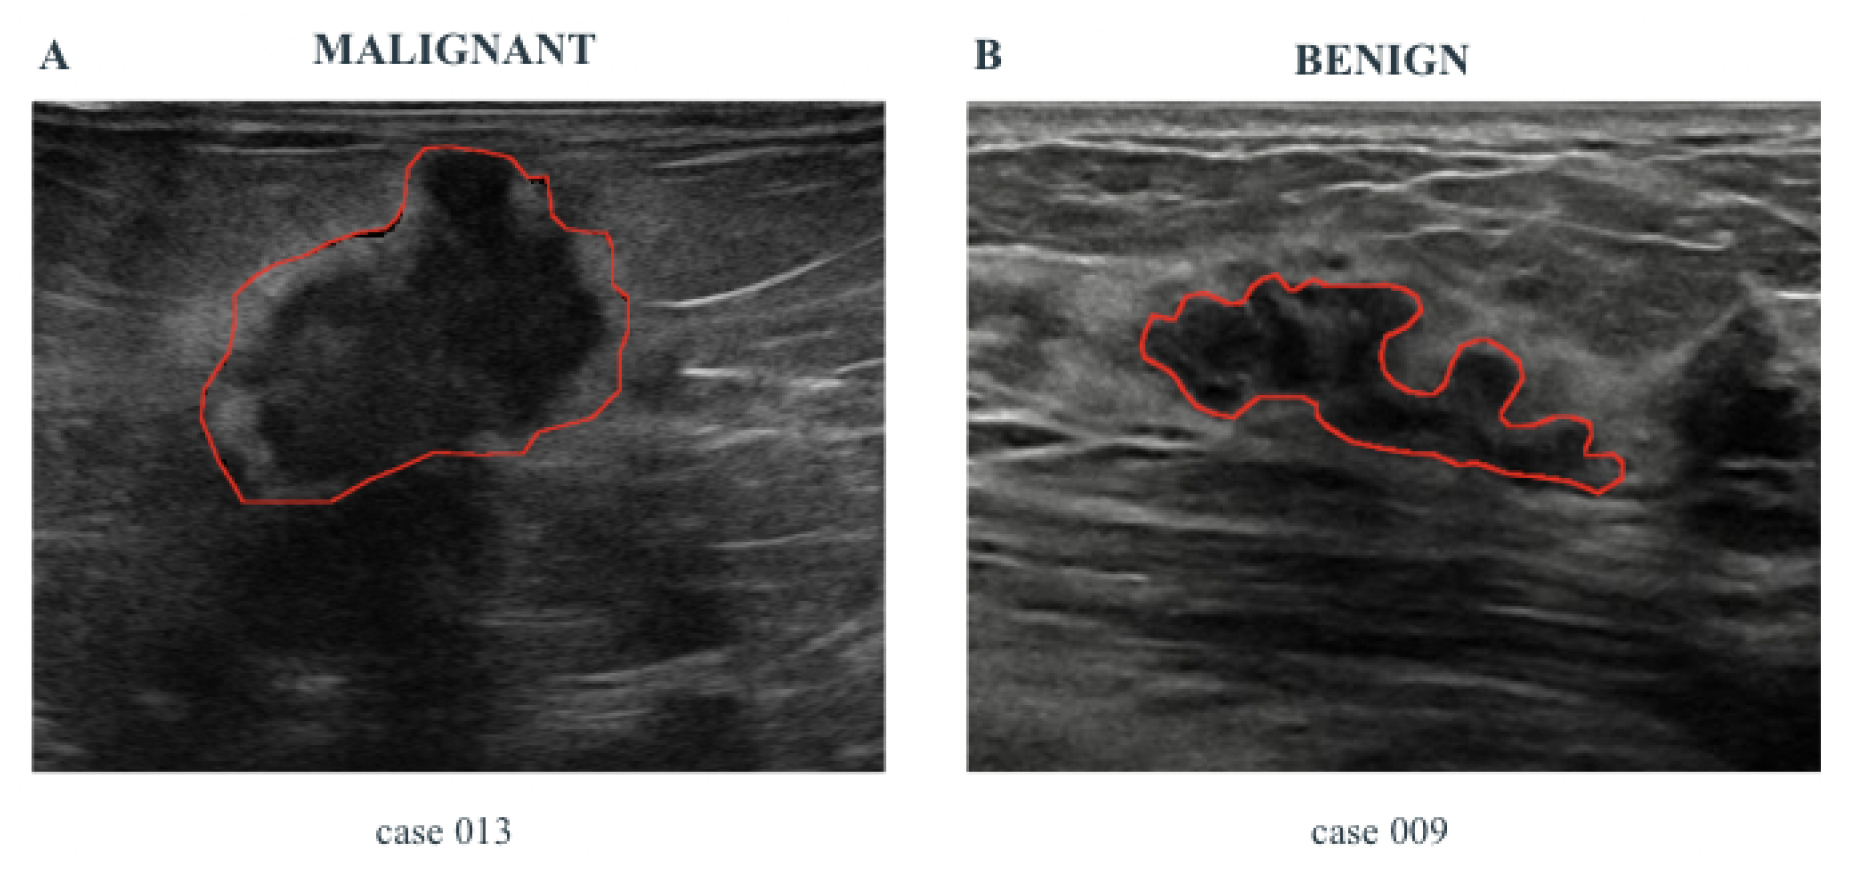

- Some specific features related to the pathology, namely Pathological Features (PF), are automatically extracted from the images, by using properly designed Computer Vision algorithms. These features are shown to the healthcare professionals and are useful to support the diagnosis.

- A risk assessment, computed by using suitably designed ML algorithms. For the computation of AI-based risk assessment, the ML methods use a set of features automatically extracted from ultrasound images, larger than PF, and called Hand-crafted Features (HF).

| Major Axis, Minor Axis | Provides intuitive size and shape information |

| Perimeter Regularity | Irregular contours may be indicative of malignancy |

| Orientation | An angle greater than 45° may suggest a malignant nature |

| Circularity | Lower circularity can reflect irregular lesion shapes |